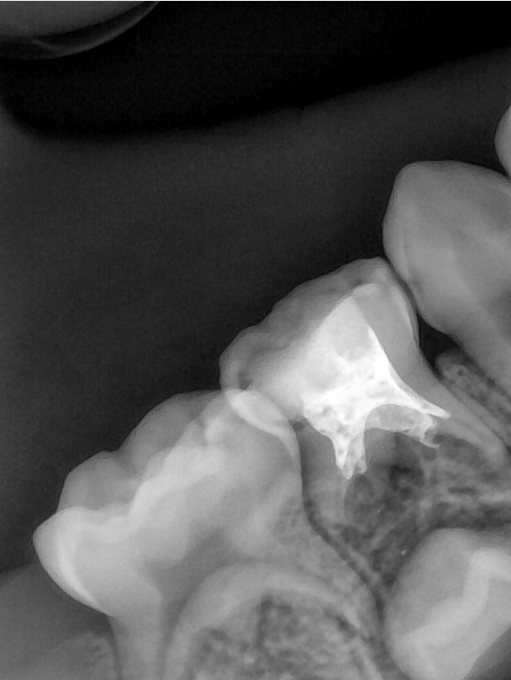

CR/DR 牙齿分割阶段记录

当前进展

- 完成了 CR/DR 牙齿相关分割训练

- 当前结果已经达到阶段预期,但仍有细节问题需要继续处理

相关测试

遇到的问题

- 训练过程中出现过 mask 下移问题

- 部分结果会出现 box 填充异常

- mask 边缘仍然有比较明显的锯齿感